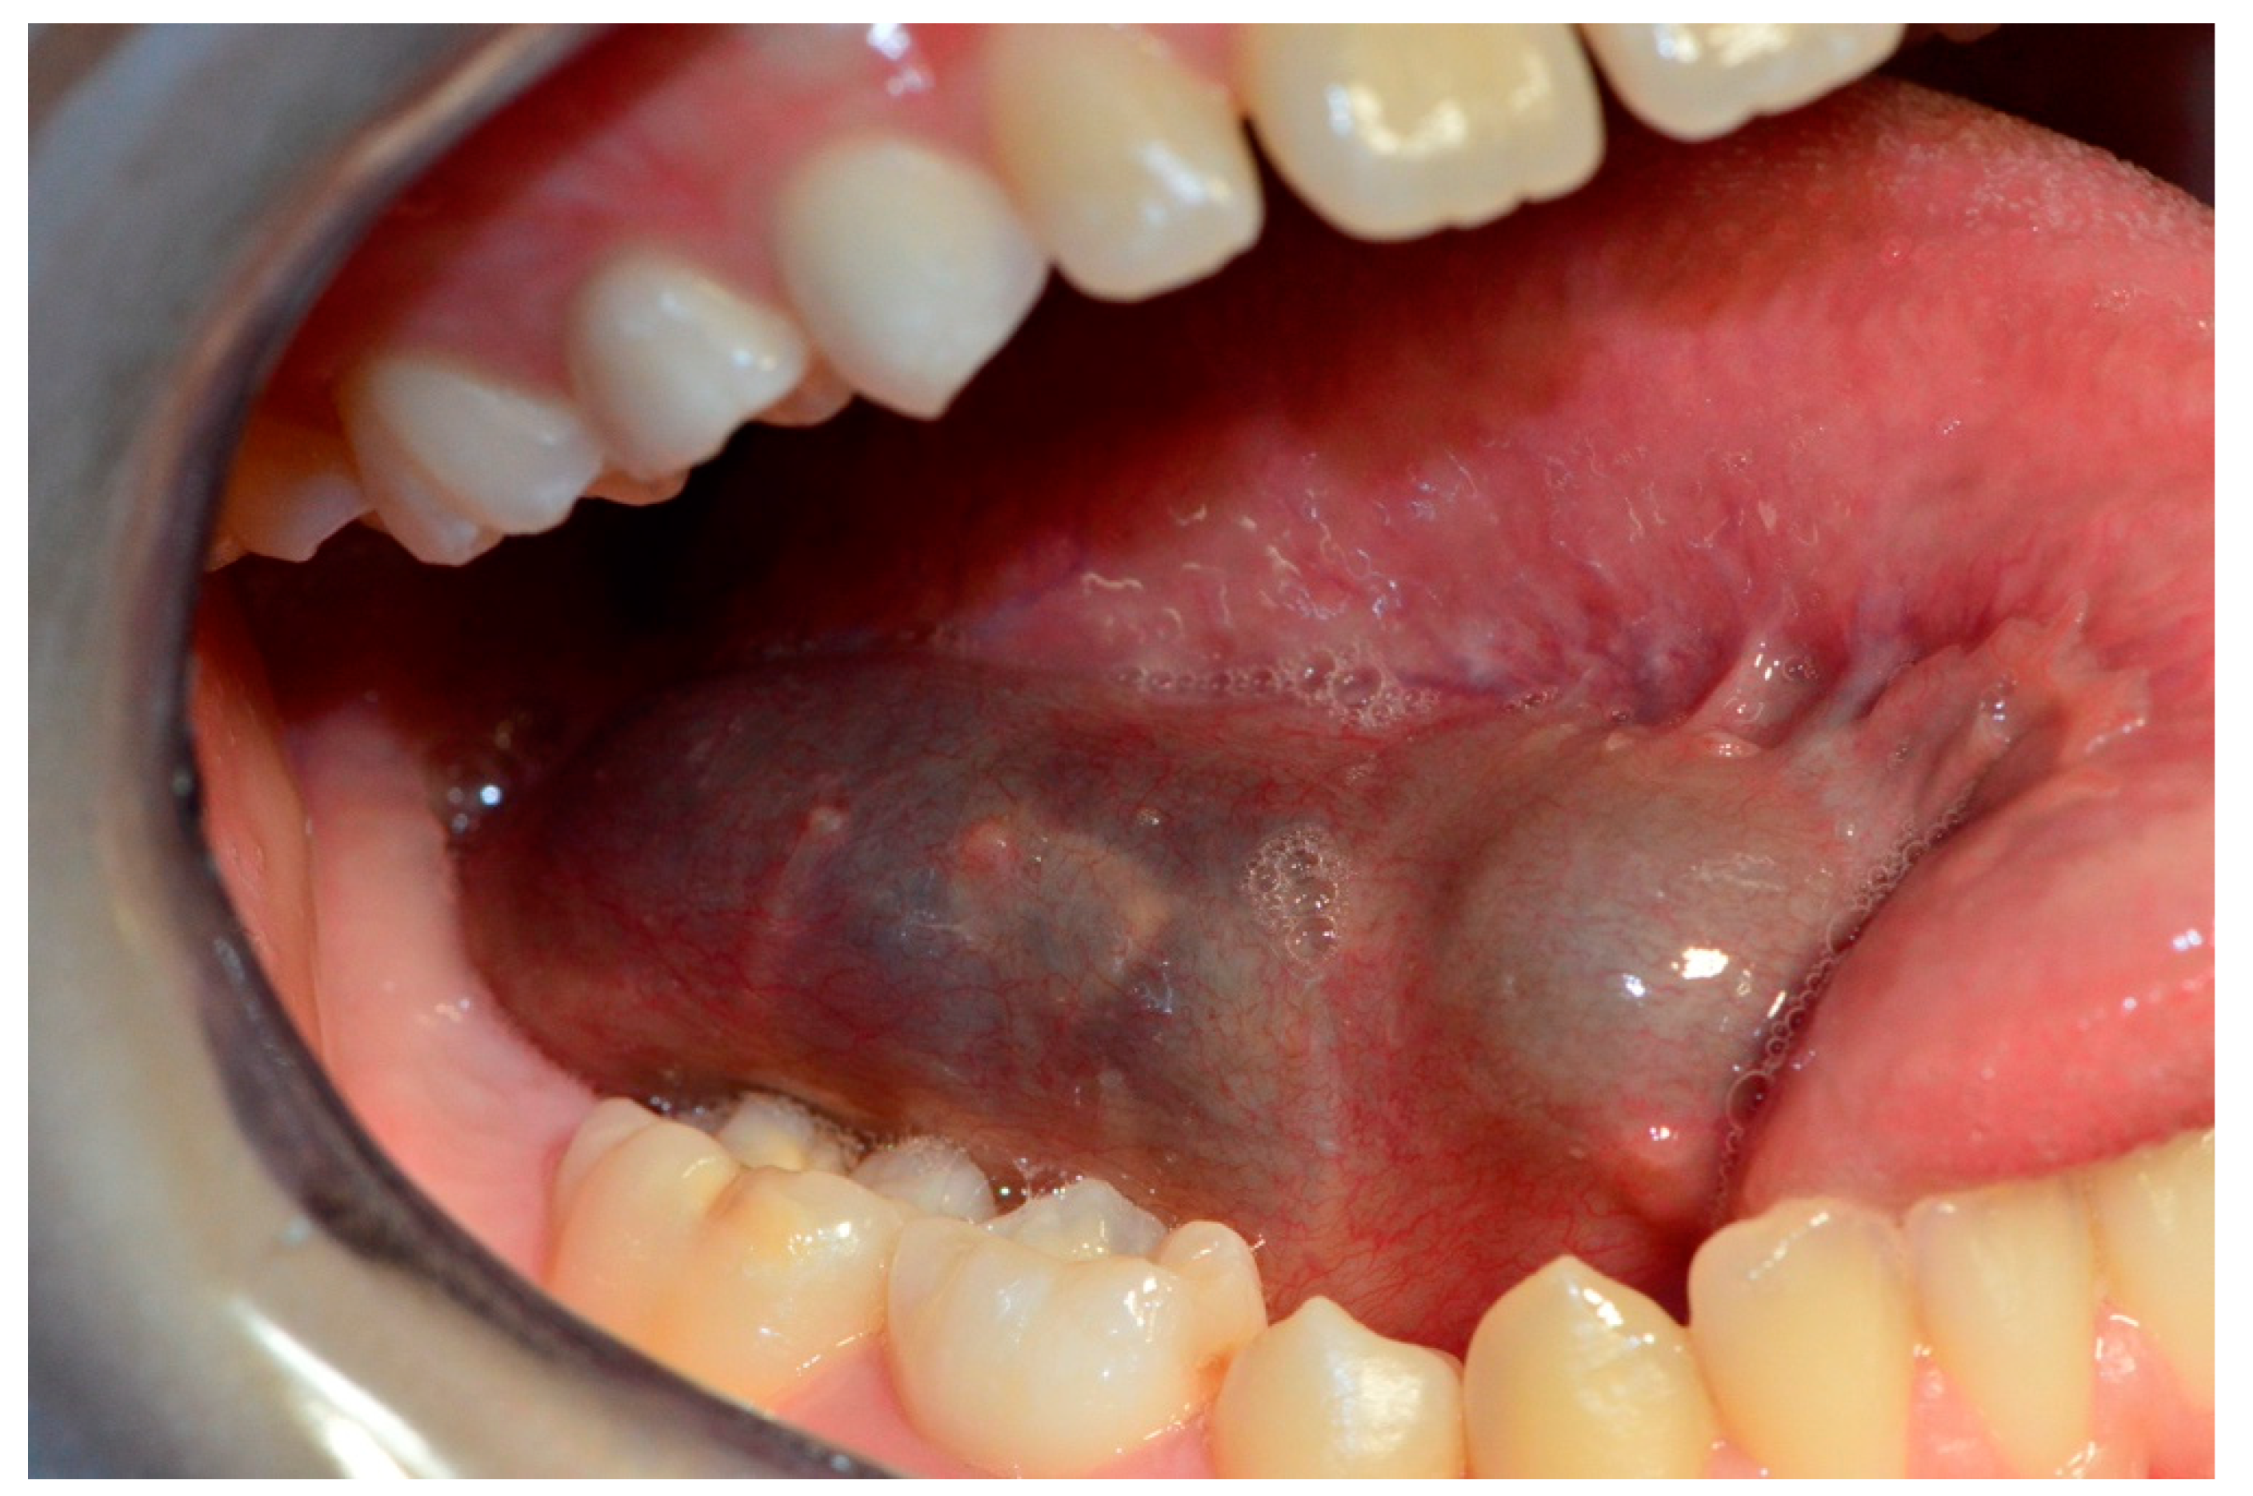

2. Case Report